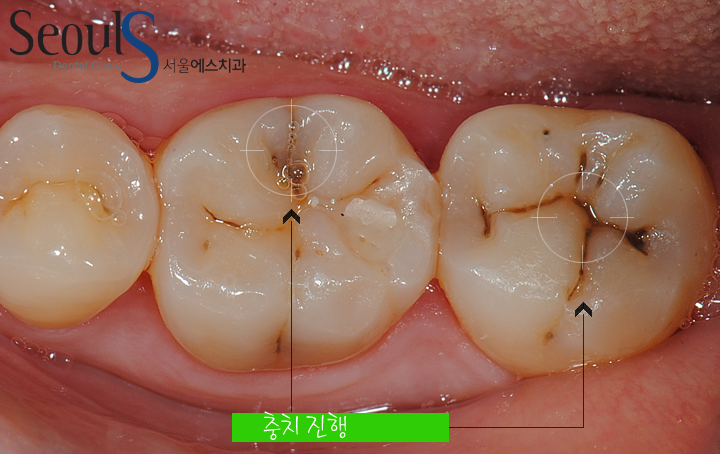

원으로 표시한 부분을 보시면 어금니 씹는면에 충치가 진행되고 있습니다

어금니 씹는면에는 쏙~~ 들어간 부분이 있습니다

이곳을 열구라 말하는데요

이곳에 음식물이 들어가고 치솔질 할때 제거 되지 않으면 충치가 진행됩니다

치아 씹는면에 충치가 진행되고 있습니다

치아 씹는면을 확대한 모습입니다

치아 표면, 쏙~~ 들어간 골(열구)을 따라 충치가 진행되고 있습니다

어금니 씹는면 충치는 대부분 열구속으로 음식물이 들어가 진행되고

열구는 개개인마다 깊이가 달라 평소 올바른 방법으로 칫솔질을 열심히 하는데 충치가 잘 생긴다면

열구의 깊이를 의심해 보시고 충치 예방을 위해 열구를 메우는 치료를 생각해보셔도 좋을것 같습니다